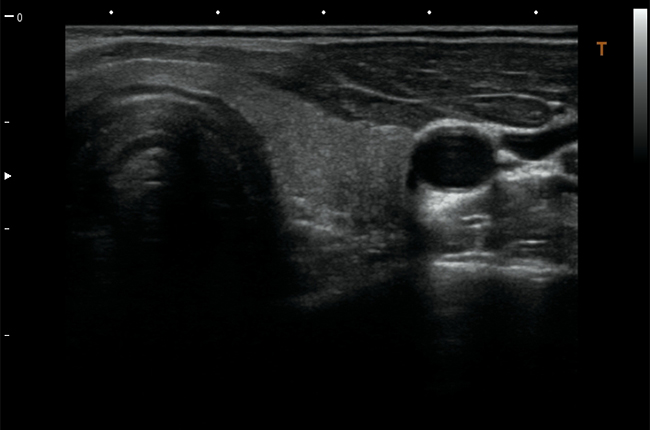

Поверхневі органи та малі структури